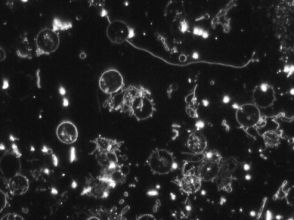

Levend Bloed Analyse

Levend bloed analyse is heel geschikt voor het herkennen van stofwisselings- en immuunsystemen. Door middel van het afnemen van een paar druppeltjes bloed via een vingerprikje, kunnen we heel veel aan jouw bloed aflezen. Er wordt gewerkt met een preparaat, waarin de witte en rode bloedcellen uren lang actief kunnen blijven. Vandaar dat er wordt gesproken van levend bloed.